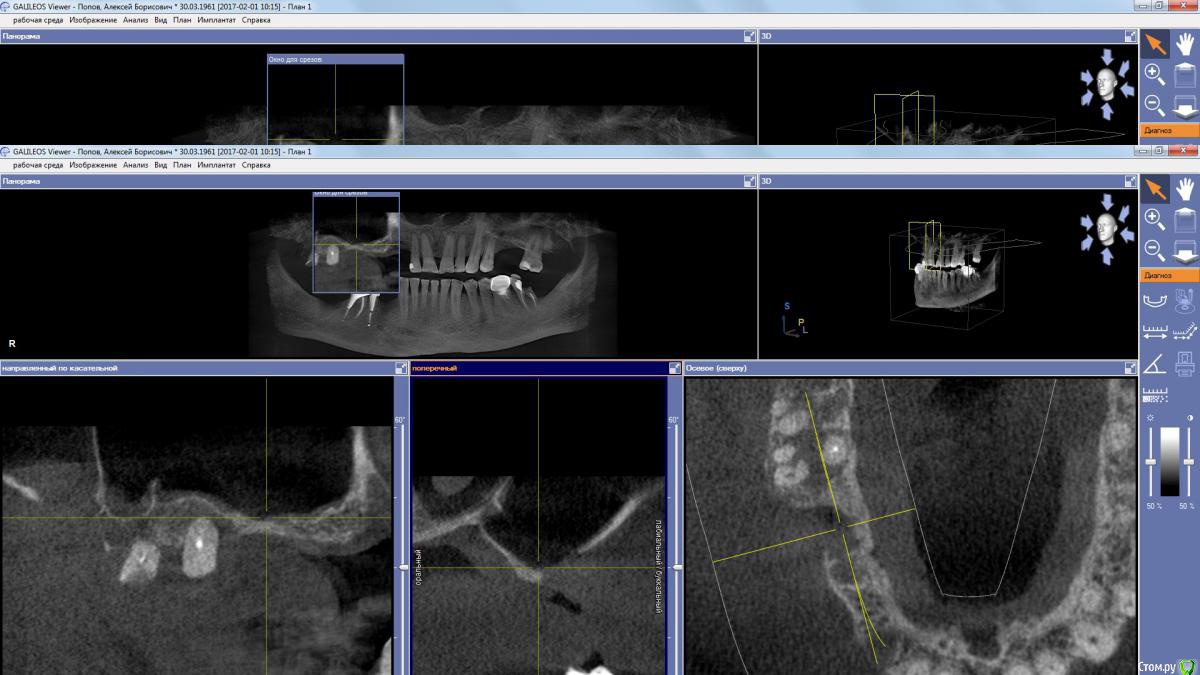

kamranchick Опубликовано 2 апреля, 2017 Поделиться Опубликовано 2 апреля, 2017 (изменено) Пациент обратился с целью восстановления жевания.удалял 16 зуб в поликлиннике, ему долбили, потом в ЧЛХ доставали что то).На кт вот такая ситуация, как посоветуете поступить? PS 1.7 и 1.8 зуб удалил. Изменено 2 апреля, 2017 пользователем kamranchick Ссылка на комментарий

stommm Опубликовано 2 апреля, 2017 Поделиться Опубликовано 2 апреля, 2017 Где окно расщеплять лоскут остро что бы часть осталась на поверхностном лоскуте, часть ввернуть в синус. Наверное можно совместить с НКР фронтальнее. З.Ы. сложно по сироне что-то планировать, самый неудобный вьюер имхо 1 Ссылка на комментарий

колесников Опубликовано 2 апреля, 2017 Поделиться Опубликовано 2 апреля, 2017 А в чем вопрос? Пазуха чистая,можно пробовать . Ссылка на комментарий

kamranchick Опубликовано 2 апреля, 2017 Автор Поделиться Опубликовано 2 апреля, 2017 Да дыры какие то и на окклюзионной поверхности и сбоку) это и отпугнуло Ссылка на комментарий

колесников Опубликовано 2 апреля, 2017 Поделиться Опубликовано 2 апреля, 2017 Дыру закрыть можно, главное из дыры отслоится без разрывов. Рубцовска ткать прочно врастает в края дефекта,я бором прохожусь по контуру дефекта и отделяю рубцовую заплатку вместе со шнейдоровой относительно легко. Ссылка на комментарий